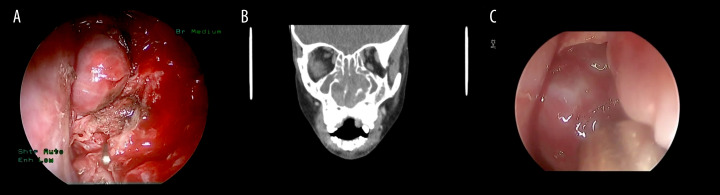

BACKGROUND Pediatric sinonasal tumors are rare, accounting for about 4% of all pediatric head and neck neoplasms. Due to their nonspecific symptoms such as nasal obstruction, epistaxis, and facial pain, these tumors often present diagnostic challenges and lead to delays in managment. Early and accurate diagnosis is crucial to optimize clinical outcomes. CASE REPORT This is a retrospective review of 4 pediatric patients with diagnosis of sinonasal tumors at a tertiary hospital in Saudi Arabia. The series includes 2 benign tumors, osteoma and juvenile nasopharyngeal angiofibroma, and 2 malignant tumors, NK/T-cell lymphoma and rhabdomyosarcoma. Diagnostic workups included nasal endoscopy, CT, MRI, and PET-CT imaging, followed by histopathological confirmation. Benign tumors were successfully treated with image-guided endoscopic excision, with no evidence of recurrence during follow-up periods of 2 and 5 years, respectively, while malignant tumors required a multimodal approach, combining chemotherapy and radiotherapy under multidisciplinary care, and showed stabilization after treatment with continued surveillance. The variety in presentation and complexity of management underscore the diagnostic and therapeutic challenges in this population. CONCLUSIONS This case series highlights the importance of early suspicion, comprehensive imaging, and individualized treatment plans in managing pediatric sinonasal tumors. The use of minimally invasive surgical techniques and preoperative embolization was effective in selected cases. The findings emphasize the role of multidisciplinary collaboration in optimizing outcomes for benign and malignant tumors. Future research should aim to develop standardized diagnostic algorithms and explore advanced diagnostic tools, such as molecular imaging, to facilitate earlier detection and improve treatment precision in pediatric sinonasal oncology.